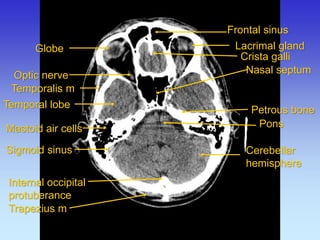

Frontal sinus

Lacrimal gland

Mastoid air cells

Medulla oblangata

Petrous bone

Rectus lateralis

Crista galli

Temporalis m

Temporal lobe

Cerebellar hemisphere

Trapezius m

Sigmoid sinus

Rectus medialis

Globe

Basillar a

Internal occipital protuberance

Optic nerve

Pons

Nasal septum

Sphenoidal sinus

Dorsum sellae

Tentorium cerebelli

Sella tursica